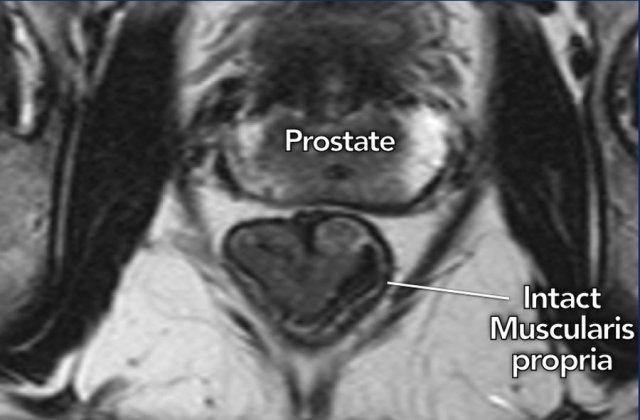

Phát hiện MRI chính:

- Lớp cơ thành nguyên vẹn(đường giảm tín hiệu bao quanh trực tràng) xác nhận khối u T1–T2

- Ba mặt phẳng(trục, đứng dọc, đứng ngang) phải thể hiện lớp cơ nguyên vẹn để dự đoán T1–T2 một cách chắc chắn

Hình minh họa

I need the actual HTML text fragment to translate. You’ve only provided “The image shows a ” which appears to be incomplete. Could you please provide the complete HTML text fragment you’d like me to translate to Vietnamese?khối u trực tràng xa cT1–2với lớp cơ niêm mạc giảm tín hiệu còn nguyên vẹn, nhìn thấy rõ ràng.